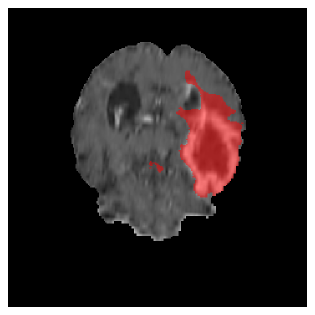

Appendix A Qualitative results

Figure 5 illustrates the segmentation evolution for the same BRATS patient in S2 sequence. The key difference here is that the best buffer-free strategy is EWC (=1), and training on BRATS data starts from episode 2 instead of episode 1 as BRATS is encountered at episode 2 in S2. The cumulative approach retains segmentation across episodes but continues to generate false positives, which become even more pronounced in the final episode. The naive approach, lacking a CL mechanisms, completely overrides previous knowledge, leading to failed segmentation in later episodes. EWC (=1) approach initially maintains segmentation but experiences a sharp decline in episode 4, where it fails to segment the tumor. In the final episode, it undersegments the lesion, missing a significant portion of the tumor. In contrast, the proposed approach consistently preserves segmentation across episodes. While initially introducing false positives, it gradually refines predictions, retaining the tumor region while minimizing misclassifications. It maintains clear tumor delineation by the final episode, demonstrating effective knowledge retention and adaptability throughout training.